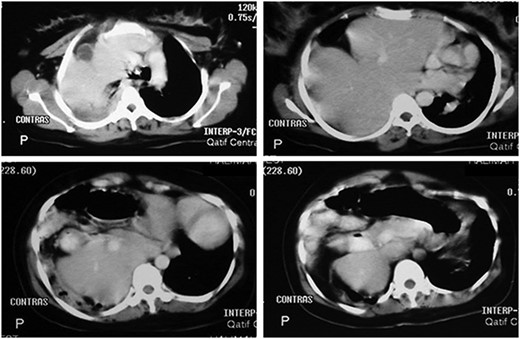

Her routine laboratory investigations including white cell count were normal. Electrocardiogram showed sinus tachycardia. Chest x-ray showed homogeneous opacity occupying the right hemi-thorax, and bowel loops were seen above the right chest with obvious mediastinal shift to the left side (Fig. 1). Abdominal computed tomography (CT) scan with contrast

Abdominal CT scan with contrast showing the entire liver and some bowel loops occupying the right hemi-thorax.

showed the entire liver and some bowel loops in the right hemi-thorax (Fig. 2). The impression was right diaphragmatic herniation, although ruptured right hemidiaphragm was entertained despite the negative history of chest trauma.